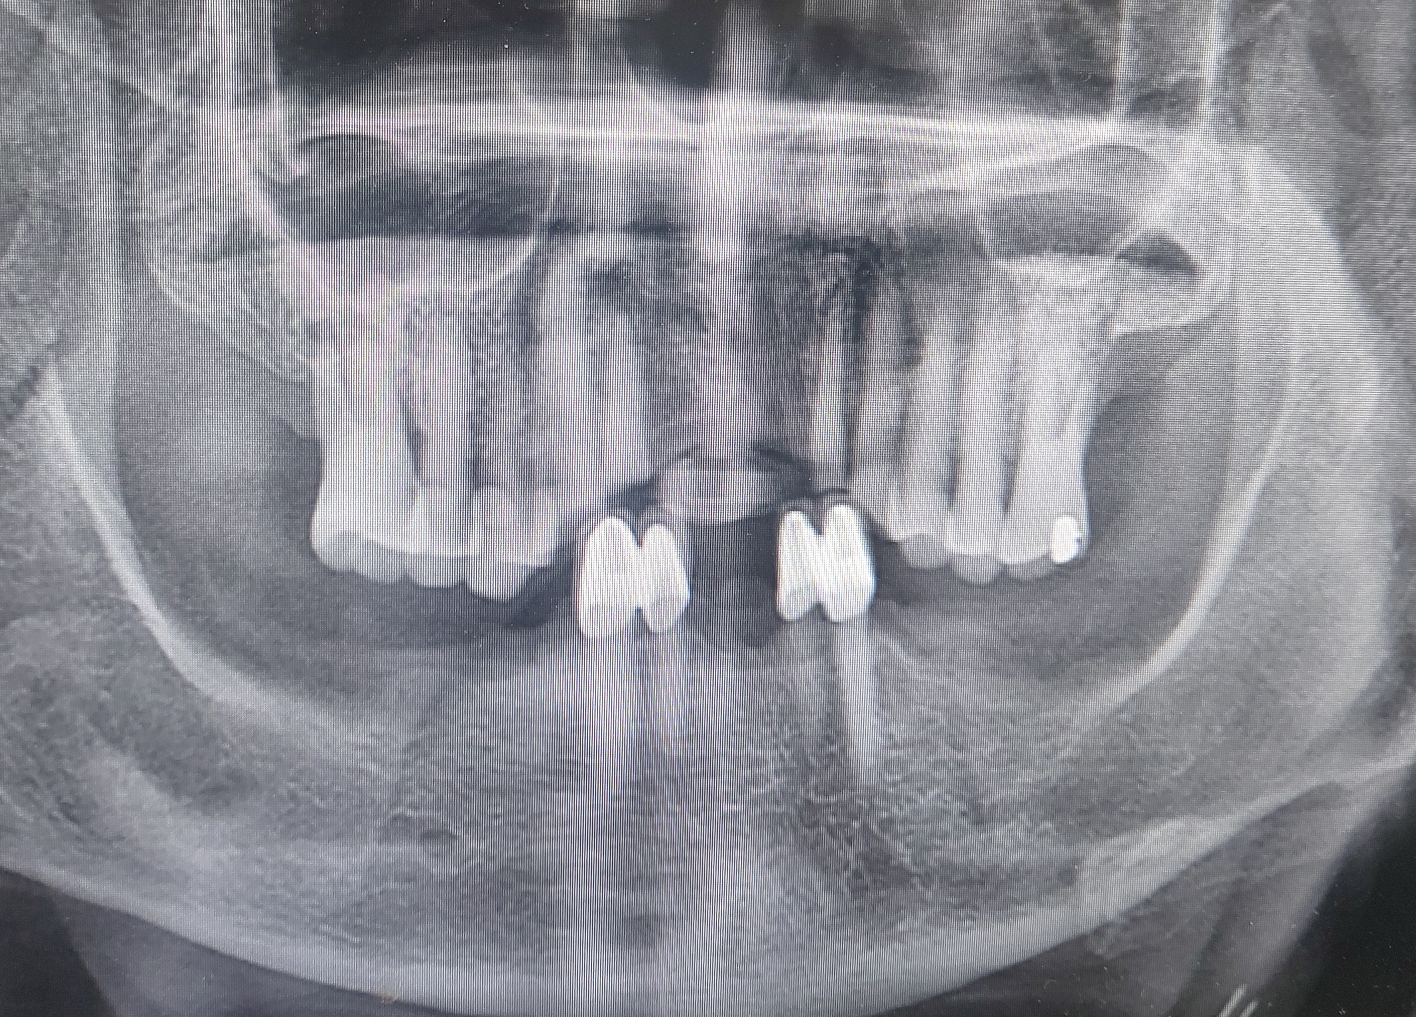

이번 환자분은 85세 어르신으로 앞니 전치부의 브릿지 파절로 내원하셨습니다. 환자분 굉장히 고령이시고 메디컬 히스트로 때문에 타치과에서는 발치를 포함하는 치과 치료에 어려움으로 포기하여서 저희 병원에 내원 하셨습니다.

환자분과 대화로 느낀점은 굉장히 연세에 비해 건강해 보이셨고 특별히 임플란트를 진행하기에 무리가 없어 보였습니다. 환자분 병력에 관하여 관계 병원 선생님들과 연락하여서 정확히 확인 후 수술에 임했습니다.